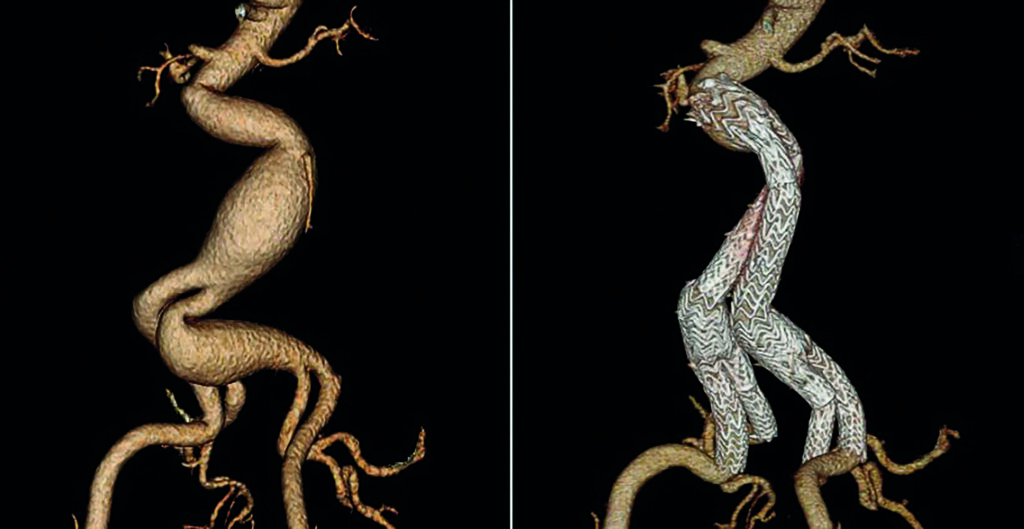

Over the next two decades, Gore developed and studied additional solutions within its EVAR portfolio, receiving approvals for larger trunk and contralateral limb diameters, an iliac branch device, and a next generation of the EXCLUDER® device that is conformable and offers optional angulation control—allowing physicians more treatment options to consider for their patient’s anatomy.